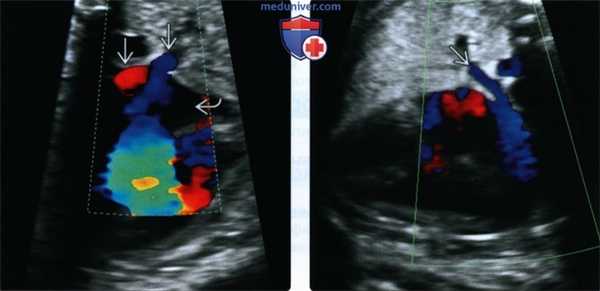

(Слева) Срез через выносящий тракт сердца (плоскость четырехкамерного среза наклонена кпереди). Видны параллельно расположенные магистральные сосуды, выходящие из ПЖ. Легочная артерия (узнаваемая за счет рано отходящих ветвей) находится позади аорты, что характерно для транспозиции.

(Справа) ЦДК в той же плоскости. Визуализируются аорта и легочная артерия, обе выходят из ПЖ В данном случае имеется удвоение выходного отверстия ПЖ - характерная находка при ППИ.

(Слева) Четырехкамерный срез, увеличенное изображение. Визуализируются левые легочные вены, впадающие в расположенное слева предсердие. Данное наблюдение не позволяет утверждать о нормальном строении всех легочных вен - необходимо исследовать правые легочные вены, чтобы исключить частичный аномальный дренаж легочных вен.

(Справа) Тот же случай. Легочная вена, идущая от правого легкого, впадает в предсердие, расположенное справа. При ЛПИ легочная вена от правого легкого направляется к расположенному справа предсердию, а от левого легкого - к ЛП, поскольку морфологически оба предсердия являются «левыми».